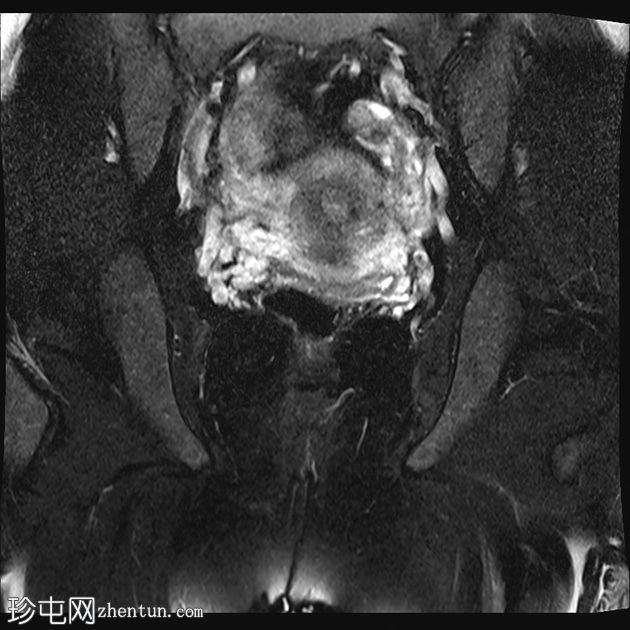

冠状位

T2加权像

MRI特征符合剖宫产术后瘢痕子宫内膜异位症,表现为特征性T1高信号伴T1FS持续存在,T2低信号伴内部高信号灶,病灶边缘浸润于腹前壁肌肉内,以及对比增强。

该病灶累及腹白线并浸润腹直肌,主要位于中线左侧,耻骨联合及结节处腹直肌起点上方。

影像学表现符合病灶内出血成分,提示既往剖宫产瘢痕处存在异位子宫内膜组织。

子宫可见剖宫产瘢痕灶。

未见明确的腹膜内或皮下软组织侵犯。